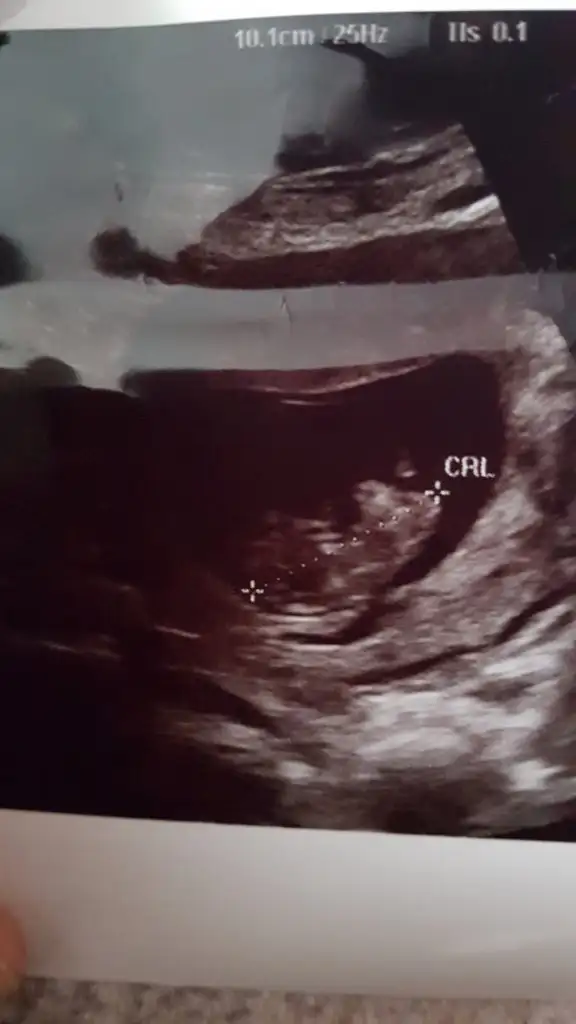

Nub için 11 yada 12 hafta kese için 6 yada 7 hafta usgnub icin erken ama kese pozisyon vs gore tahmini olan var mi? 9+4

Eki Görüntüle 2546197 Eki Görüntüle 2546198

Sen ne tahmin ettin arkadaşa ben erkek nubu gördüm umarım pozisyon değiştirmez bi arkadaşın hatta 2 arkadaşın dr ısrarla birine kız birine erkek demiş her ikiside 15 ve 16 haftasında benim tahminlerim tutu8 899eylulgelini burayada atarsan tahmin alırsın

Ben de çok net erkek dedim kafa duruş ama belli olmaz tabii senin ne dediğini de sordum hattaSen ne tahmin ettin arkadaşa ben erkek nubu gördüm umarım pozisyon değiştirmez bi arkadaşın hatta 2 arkadaşın dr ısrarla birine kız birine erkek demiş her ikiside 15 ve 16 haftasında benim tahminlerim tuturabbim gönüllerdekini saglıkla nasip etsin inşallah